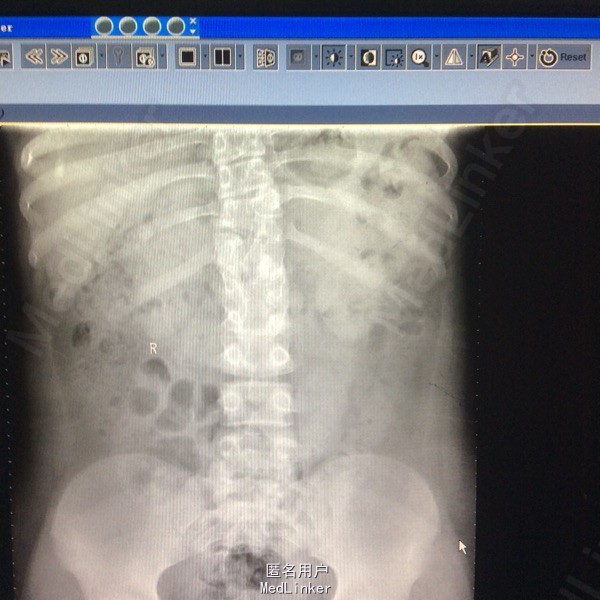

站立位腰背部疼痛5个月 五月前检查发现腰背部畸形伴疼痛,未行特殊治疗。

患者呈向心性肥胖,眼角略上斜,下颌小,上下牙间距大,闭齿音发音不清,性早熟,外阴幼稚,大小阴唇发育不良,手脚小胖,指端纤细,余查体无明显异常。 辅助检查:胸9-10胸12-腰1椎体融合、胸11呈半椎体,椎管内脊髓未见明显信号异常.

胸椎半椎体畸形 左侧第10肋骨缺如 隐形骶椎裂 双下肢膝外翻 双下肢肌挛缩症 脊柱畸形术,胸5、6、8、9腰1-2-3双侧椎弓根螺钉,去除胸11-12后方椎板,胸12半椎体及上下间隙间盘去除,椎间隙植骨。